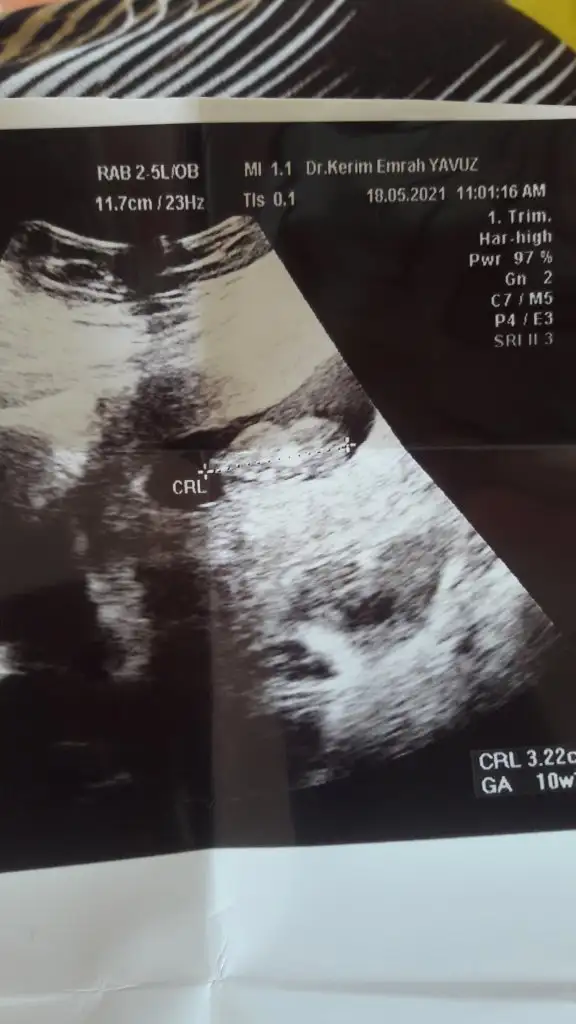

Paralel yakın görünüyor kız sankiIkra meyra merhabaaa Canım :) Arkadaşımın bebisinin fotosunu atiyorum.Sana zahmet tahminde bulunabilirsen çoooook sevinirim :) Şu an 12+2 :)

Kız görünüyor kaç haftalık USG 11 12 13 haftalar olmalıMerhabaIkra meyra benim içinde bakar mısınız rica etsem ilk çocuğum olduğu için merak ediyorum :) herkes erkek dedi ama sizinde yorumunuzu çok merak ediyorum

Valla 12+1 o görüntü herkes erkek dedi ama hayırlısı bakalımKız görünüyor kaç haftalık USG 11 12 13 haftalar olmalı![]()

Dikkatli bakar mısınız lütfen sanki bir çıkıntı var gibi pipiye benziyorKız görünüyor kaç haftalık USG 11 12 13 haftalar olmalı![]()

Evet baktım acısı paralel olarak iniyorDikkatli bakar mısınız lütfen sanki bir çıkıntı var gibi pipiye benziyor

Kız görünüyorYani ne demek oluyor peki

Erkek görünüyorbenim usg leri de yorumlayabilir misiniz acaba![]()

Peki kesin midir değişir mi sonradan bu hafta eşime sürpriz yapmayı düşünüyorumdaKız görünüyor![]()

Tahminim kız ama yinede Dr bekleyinPeki kesin midir değişir mi sonradan bu hafta eşime sürpriz yapmayı düşünüyorumda